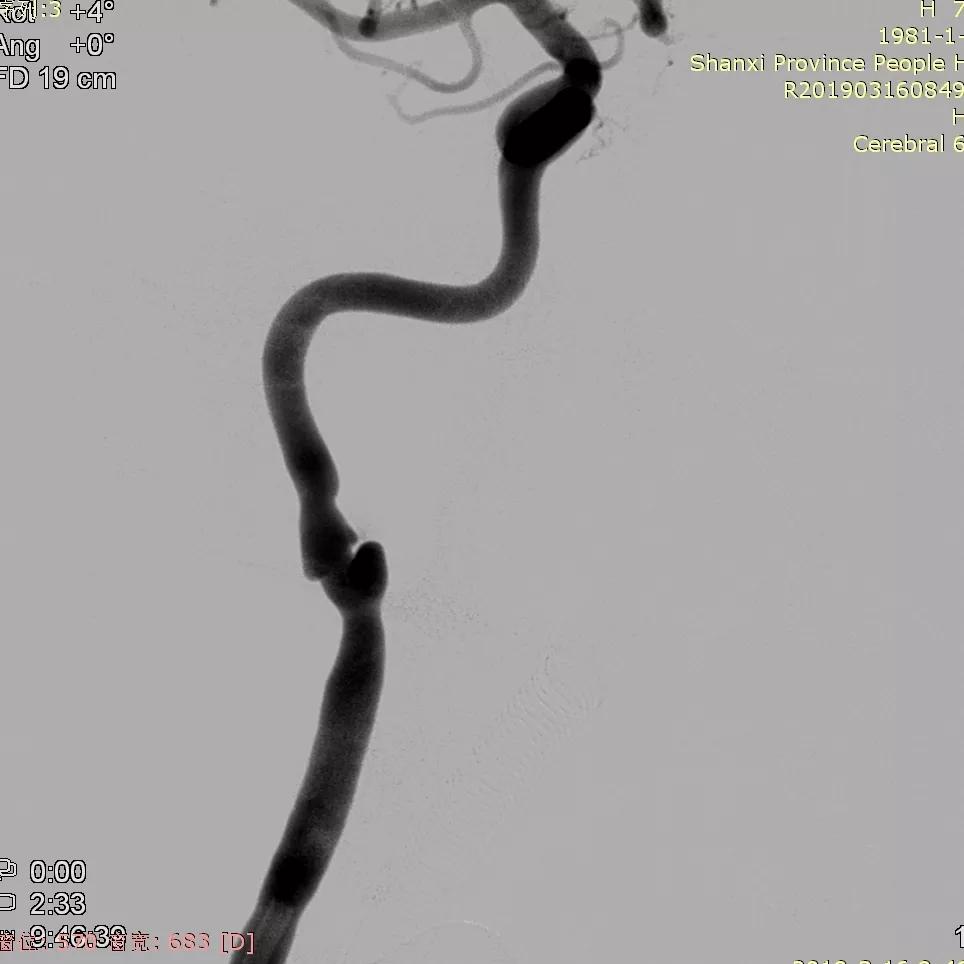

男,38y,因“间断头痛、头晕13天余”来院。

患者晚间睡觉时突感头痛,呈胀痛,持续时间月10min,后自行缓解,伴头晕,无恶心呕吐,未予处理。次日,再次出现上诉症状。入院前2日再次出现头痛、头晕。外院头颅CTA示右侧颈内动脉夹层动脉瘤。

全脑血管造影可见右侧颈内动脉颈段末段夹层动脉瘤。

Traxcess 14微导丝导引Headway 17支架导管,远端顺利送入右侧颈内动脉远端,尾部连接Y阀1个,压力带1个(非肝素)。

经支架导管,置入Tubridge® 4.5×35mm,顺利释放,位置良好。

复查造影,各血管及分支通畅,流速正常。手术结束。